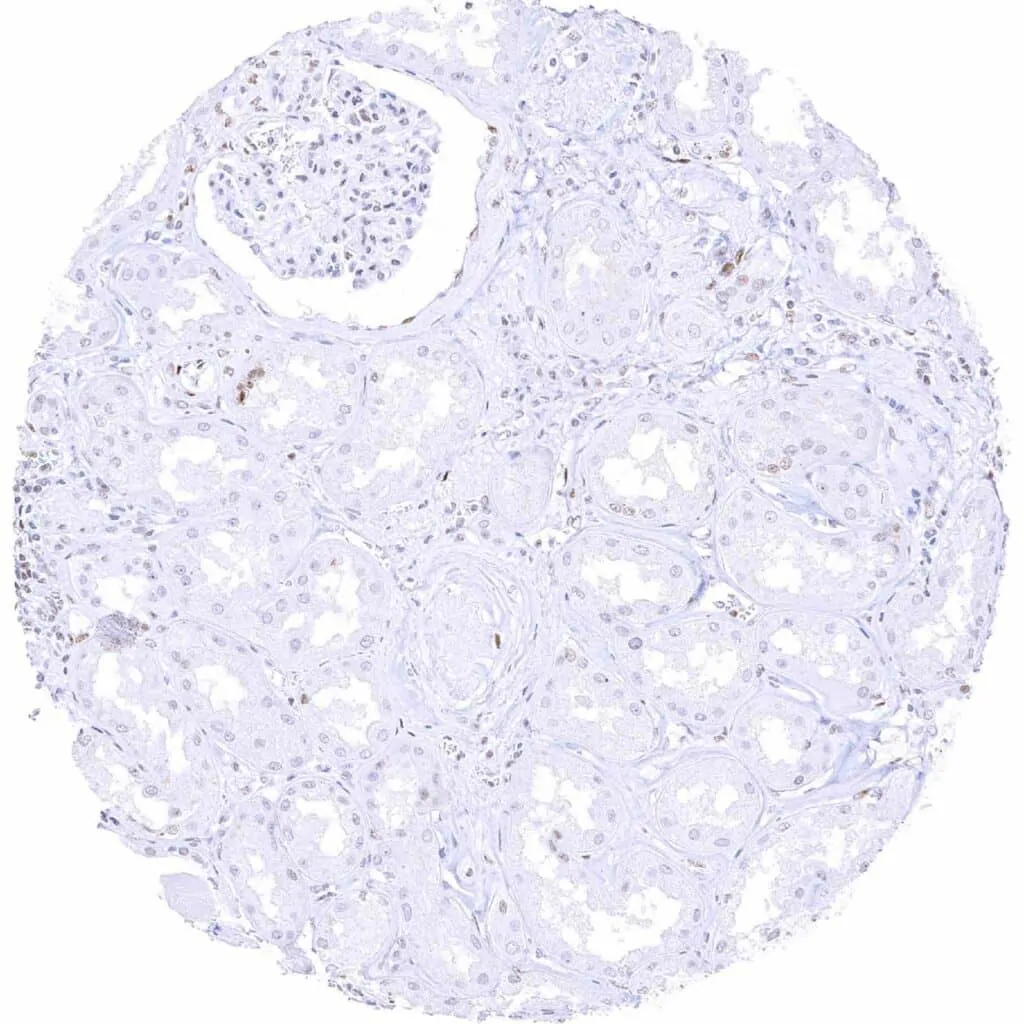

Kidney, cortex – Weak to moderate staining of few glomerular cells and of cells of parietal layer of the Bowman capsule. Staining is often faint or absent in tubular cells

Kidney, medulla – TLE1 staining is often faint or absent in tubular and collecting duct cells